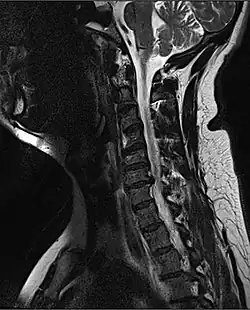

MRI of a fractured and dislocated cervical vertebra (C4) in the neck that is compressing the spinal cord